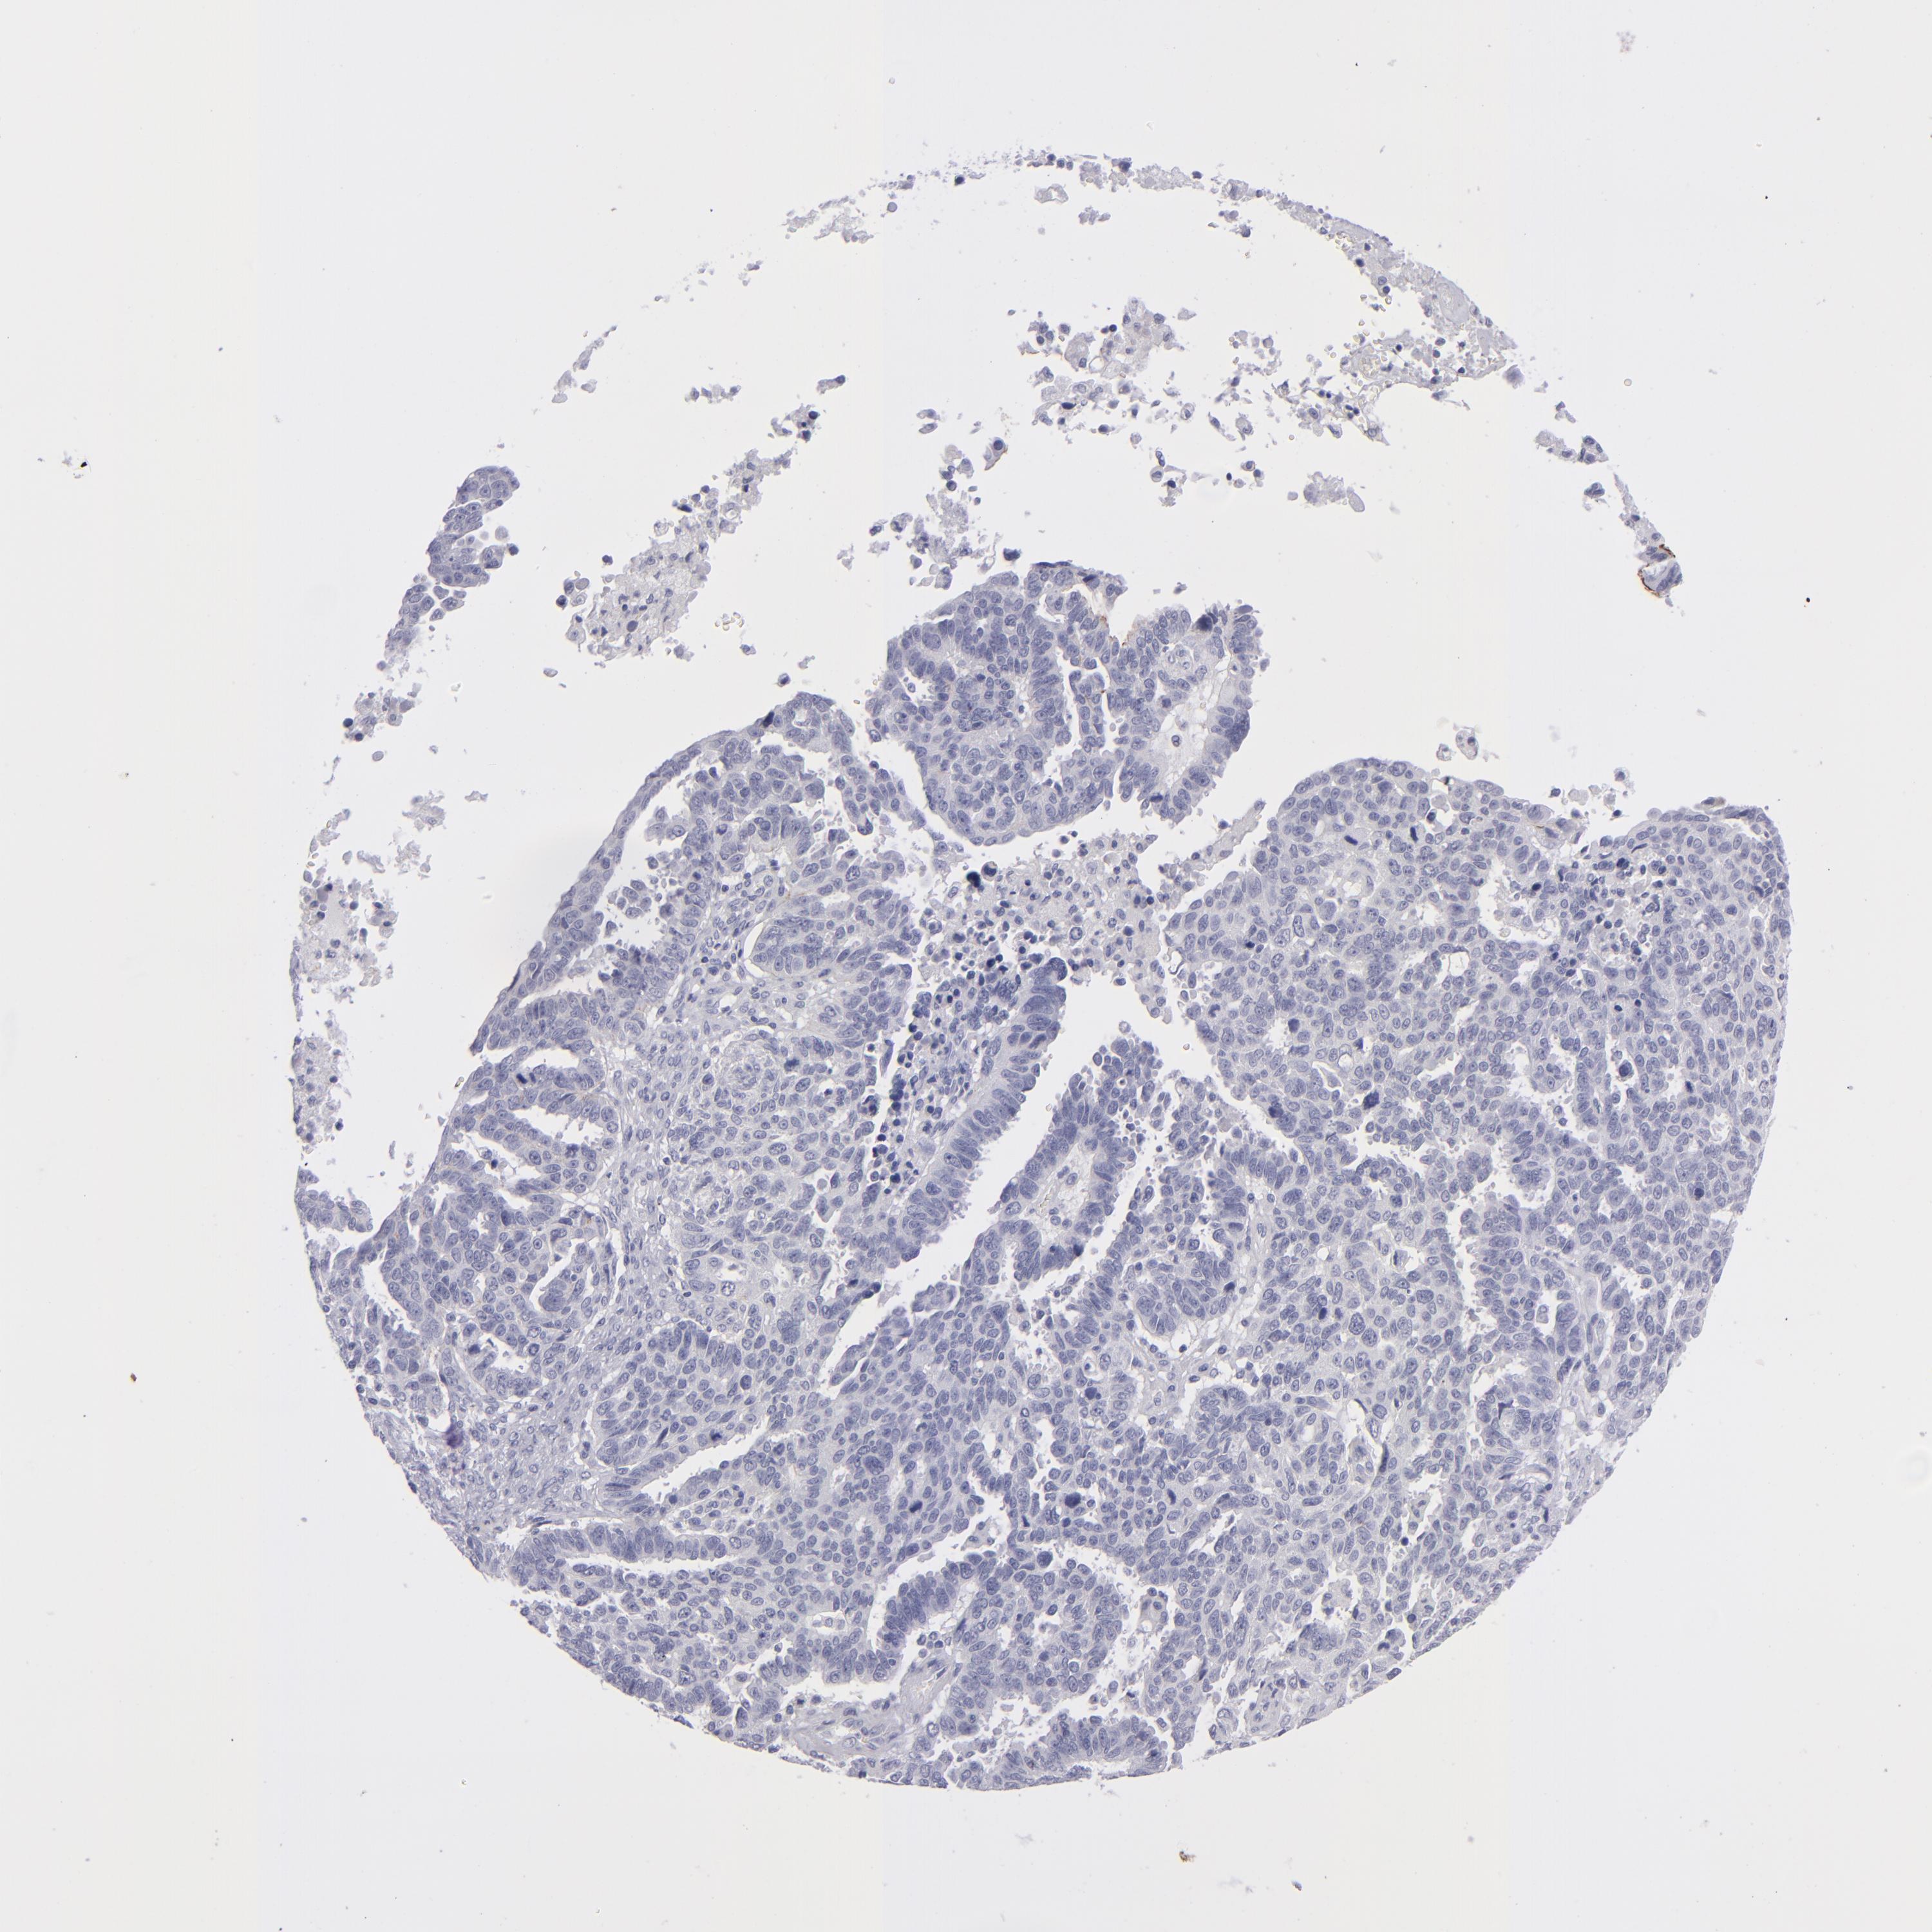

OVARIAN CANCER - Protein expressioni

A mouse-over function shows sample information and annotation data. Click on an image to view it in a full screen mode. Samples can be filtered based on level of antibody staining by selecting one or several of the following categories: high, medium, low and not detected. The assay and annotation is described here.

Note that samples used for immunohistochemistry by the Human Protein Atlas do not correspond to samples in the TCGA dataset.

Antibody stainingi

Antibody staining in the annotated cell types in the current human tissue is reported as not detected, low, medium, or high, based on conventional immunohistochemistry profiling in selected tissues. This score is based on the combination of the staining intensity and fraction of stained cells.

Each image is clickable and will lead to virtual microscopy that enables deeper exploration of all samples and also displays staining intensity scores, fraction scores and subcellular localization as well as patient and tissue information for each sample.

Antibody HPA036348

Antibody HPA036349

Antibody CAB002422

Antibody CAB005258

Cystadenocarcinoma, serous, NOS

Carcinoma, NOS

Cystadenocarcinoma, mucinous, NOS

Carcinoma, endometroid